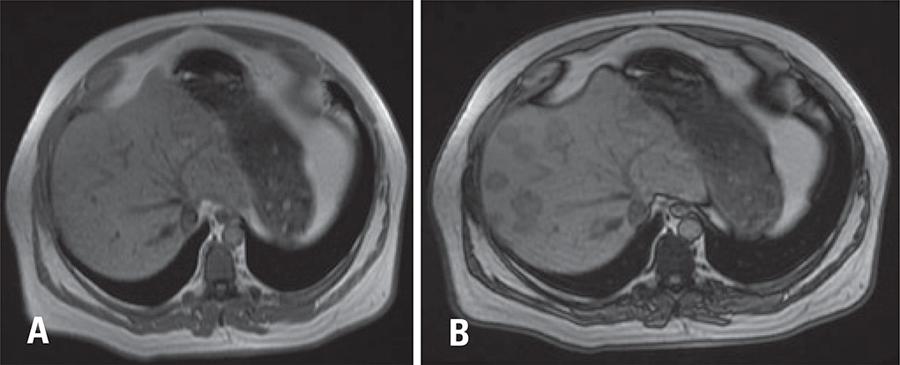

Multifocal nodular steatosis mimicking liver metastasis

We report a case of a 56-year-old male under investigation for large lytic lesion at clivus. After lesion resection, patient was referred to abdominal computed tomography scan for metastasis screening. The lesion was posteriorly characterized as chondroid chordoma at histopathology examination.

On non-enhanced computed tomography, multiple hypottenuating nodules of different sizes were seen; the largest nodule had 3.2cm. On post-contrast phases lesions had similar enhancement to adjacent liver parenchyma. However, no significant mass effect or invasiveness were seen, once vascular structures (liver veins and portal branches) crossed such nodules without dislocation or invasion. Our findings, although not pathognomonic, suggested the hypothesis of multifocal nodular steatosis.